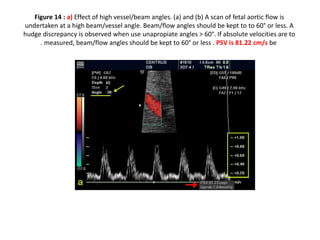

Figure 14 b) : Effect of high vessel/beam angles. (a) and (b)

A scan of fetal aortic flow is undertaken at a high beam/vessel

•

angles > 60°. If absolute velocities are to be

beam/flow angles should be kept to 60° or less .

PSV is 113.54 cm/s

Figure 14 b) : Effect of high vessel/beam angles. (a) and (b) A scan of fetal aortic flow is

undertaken at a high beam/vessel angle. Beam/flow angles should be kept to to 60° or less. A

hudge discrepancy is observed when use unapropiate angles > 60°. If absolute velocities are to

be

measured, beam/flow angles should be kept to 60° or less . PSV is 113.54 cm/s

.

Figure 14 b): Effect of high vessel/beam angles. (a) and (b) A scan of fetal aortic flow is undertaken at a high beam/vessel angle. Beam/flow angles should be kept to to 60° or less. A hudge discrepancy is observed when use unapropiate angles > 60°. If absolute velocities are to be measured, beam/flow angles should be kept to 60° or less . PSV is 113.54 cm/s .